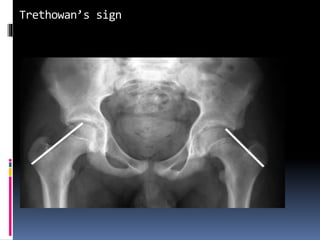

 PRESLIP STAGE:

 Minimal slip – absence of normal shoulder on upper aspect of neck & head-

trethowan sign ;line drawn along superior surface of neck will pass above

head.